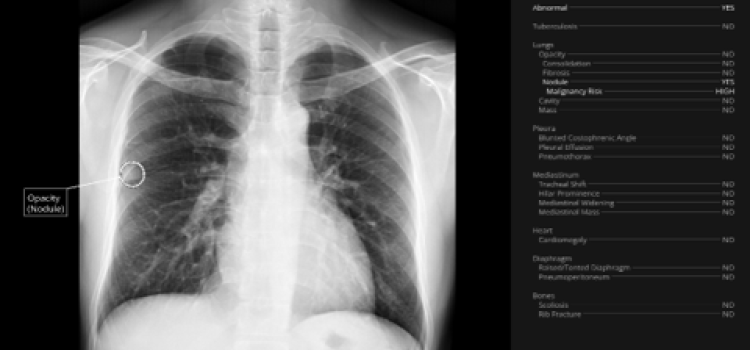

News and new technology innovations concerning how imaging technology for the lungs. This includes computed tomography (CT), X-ray and ultrasound imaging of the lungs to diagnose and monitor treatment for lung cancer, COPD, pulmonary embolism (PE), pneumonia, tuberculosis and COVID-19 can be found on this channel.

Sept. 8, 2025 — A new clinical case study, presented by Qure.ai and Hacettepe University, Turkey, at the IASLC World ...

Sept. 11, 2024 — A new study introduced at the International Association for the Study of Lung Cancer (IASLC) 2024 World ...

July 22, 2024 — Healthcare artificial intelligence (AI) systems provider, Qure.ai, has announced its receipt of a Class ...